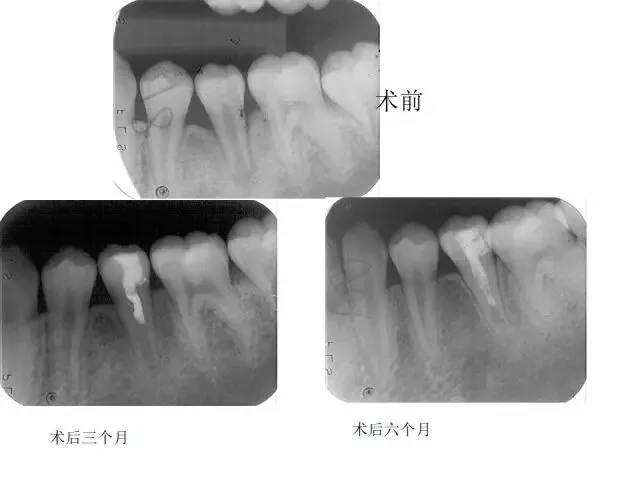

>PPT典藏 | 根尖诱导成型术

PPT典藏 | 根尖诱导成型术